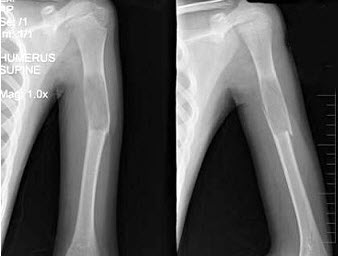

121、单项选择题

男,17岁,来右前臂疼痛,肿胀近2年,2周前疼痛加剧,查体右前臂压痛明显,皮肤稍显红肿,结合图像,最可能诊断是()

A.骨囊肿

B.骨巨细胞瘤

C.动脉瘤样骨囊肿

D.软骨瘤

E.骨血管球瘤